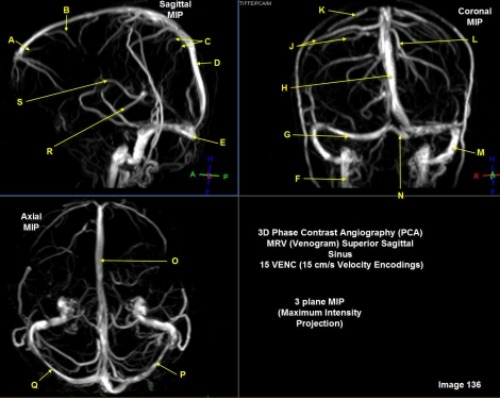

Letter C in Image 133 is pointing to:

B. Common carotid bifurcation

Letter F in Image 133 is pointing to:

D. Thoracic aorta

Letter K in Image 133 is pointing to:

D. Internal carotid artery

Letter E in Image 133 is pointing to:

B. Left subclavian artery

Letter D in Image 133 is pointing to:

A. Vertebral artery